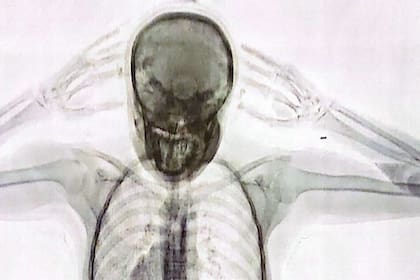

Impactante imagen: así se ve en un escáner de rayos X el cuerpo de una “mula” con 78 cápsulas de cocaína

A. S. F. llegó al aeropuerto internacional de Ezeiza para viajar a Barcelona, España, en vuelo de la línea aérea Level. Pero nunca llegó a subirse al avión. Cuando estaba por embarcar fue entrevistada por agentes de la Policía de Seguridad Aeroportuaria (PSA). La joven, de 20 años y domiciliada en el barrio de Villa del Parque, respondió de forma “incongruente” y “dubitativa”. Poco después quedaría internada y detenida: las imágenes del escáner de rayos X revelaron la “presencia de cuerpos extraños en el organismo”. Ella misma confesó que llevaba “un paquete introducido por vía vaginal”. Eran 78 cápsulas con cocaína. La chica era, efectivamente, una “mula” de una banda narco.

“No solo respondió de forma dubitativa, también lo hizo de manera incongruente. Entonces, se decidió convocar a dos testigos y se le realizó un control corporal, no invasivo, mediante equipo de rayos x denominado Body Scan. El operador del equipo técnico visualizó una imagen dudosa en cuanto a la posible presencia de cuerpos extraños en el organismo”, explicó a LA NACION una fuente de la investigación.

“El juez Aguinsky dispuso que se realice una requisa sobre la pasajera, detectándose que presentaba, en su zona genital interna [sic], elementos extraños, manifestando espontáneamente, que transportaba un paquete introducido vía vaginal”, sostuvo una fuente al tanto del expediente.

”En el hospital, los médicos confirmaron la presencia de cuerpos extraños introducidos vía vaginal y en el sistema digestivo de la pasajera”, agregaron los informantes consultados.